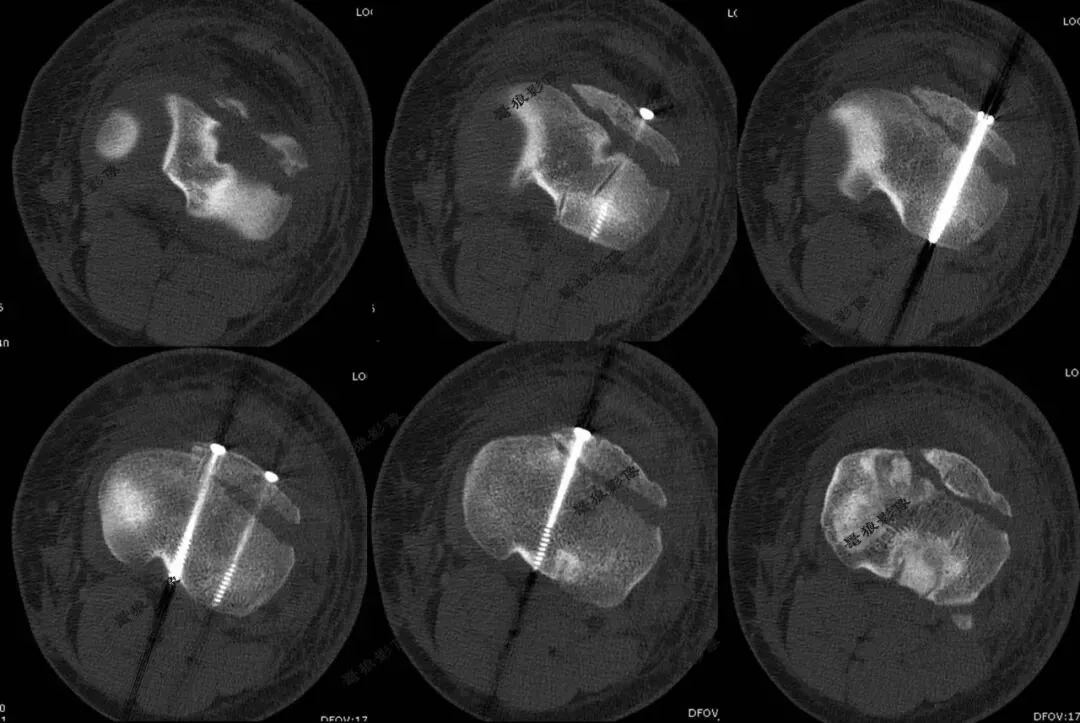

3.术后X线片:

4.术后CT:

1.常规手术:需要切开10-15cm左右切口才能复位骨折。缺点是:创伤大、疤痕大,且可能影响骨骺!

2.闭合复位手术:技术要求高,且要避开骨骺线进行固定,操作空间极小。本病例采用中医正骨+钳夹、顶棒推挤技术实现骨折闭合复位,仅3个长约0.5cm左右切口置入螺钉固定,完美复位并固定骨折。优点是:出血少、不留疤、康复快!